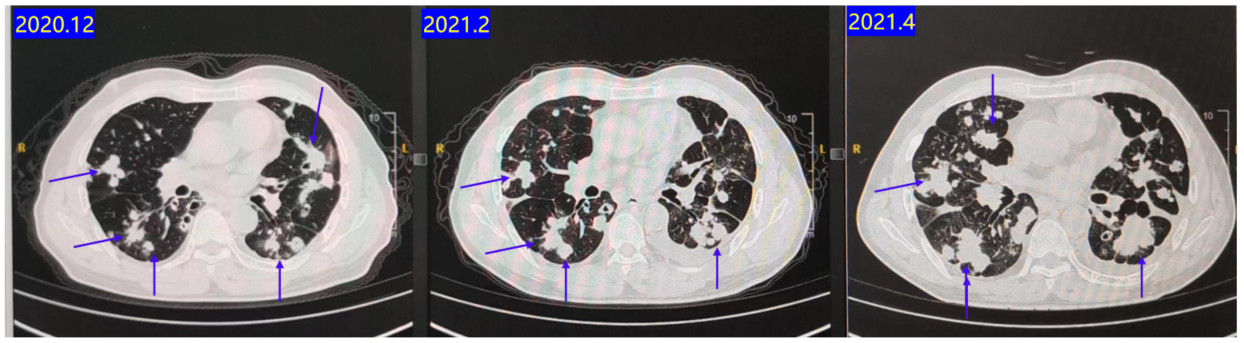

五线治疗

2021.01-2021.04:行TAS-102治疗。

疗效评估:C1评估SD,C2评估PD(图7)。PFS 3个月。